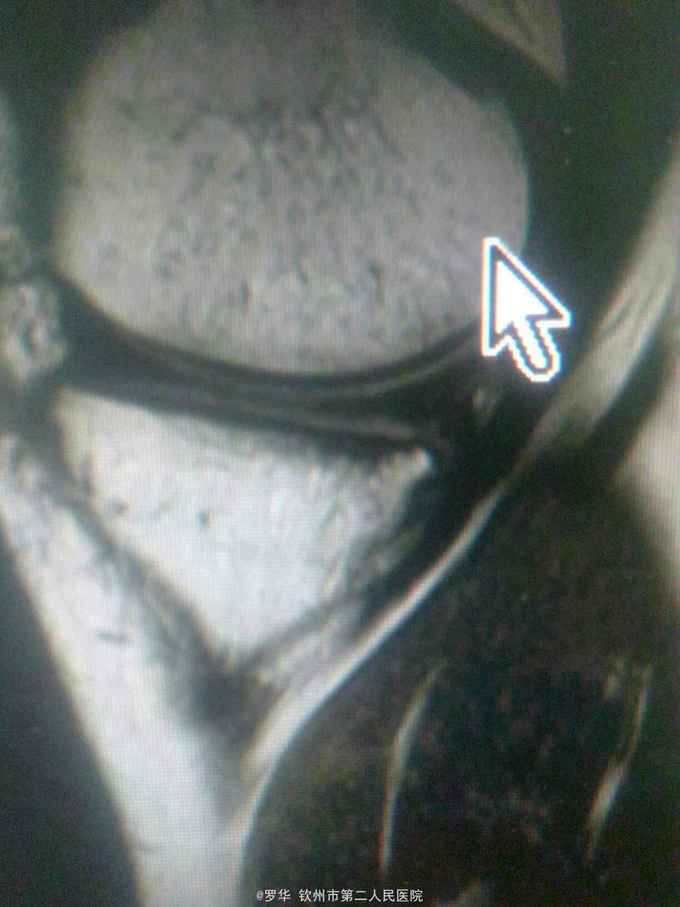

主诉:扭伤致左膝关节活动受限3月余。病史:患者男性,31岁,于入院3月余前扭伤左膝关节,致左膝关节肿痛、活动受限,尚可站立行走,但不能剧烈运动及重体力劳动,曾行磁共振检查提示左膝前交叉韧带损伤,半月板损伤,现为进上一步治疗入院。

查体:左膝关节无明显压痛,前抽屉试验阳性,侧方应力试验、麦氏征、研磨试验均阴性,膝关节屈伸活动可,余查体未见特殊。 辅查:膝关节磁共振提示左前交叉韧带损伤,左膝关节半月板损伤。

诊断:左膝关节前交叉韧带断裂,左膝关节半月板损伤。 治疗:予硬外麻下行左膝关节前交叉韧带重建术。